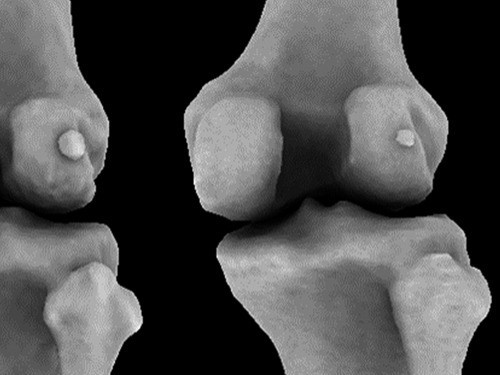

Анатомия: Блоки и сесамовидные кости в деталях